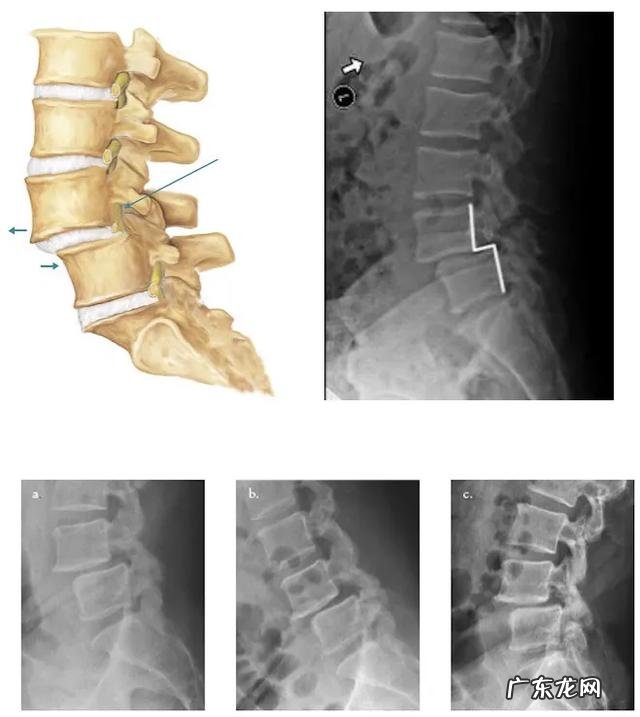

看滑脱的程度,椎体滑脱分为轻度中度和重度,有向前、向后和侧面滑脱,通常向前较多,因为腰椎的曲度是向前的